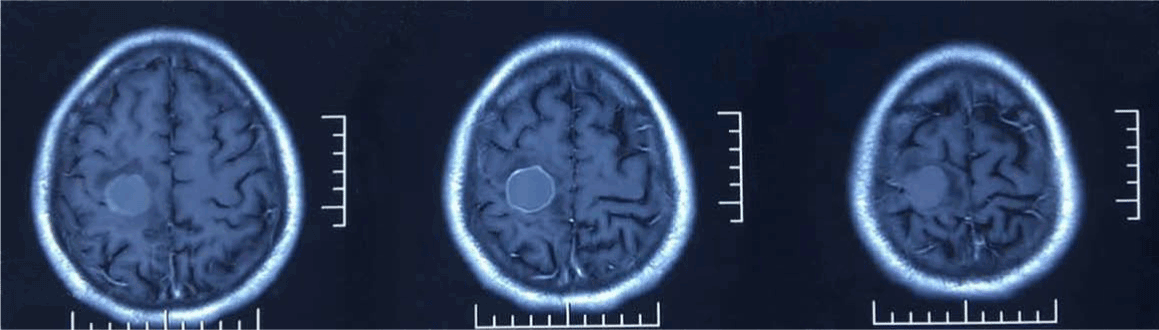

A 60-year-old Chinese man was admitted to Hospital with the history of intermittent convulsion of left upper limb with numbness of left lower limb for more than half a month, without headache, dizziness, nausea, vomiting and other symptoms. Brain magnetic resonance imaging (MRI) revealed an occupying lesion in right frontal lobe (Figure1 A-C), then brain metastasis and gliomas were considered. A chest X-ray was taken, and no abnormality was detected. Tumor markers were slightly higher and results were summarized. Subsequently, he was referred for an FDG PET/CT imaging to evaluate the whole-body, the images revealed a low-density lesion in right frontal lobe with distinct borderline, and FDG uptake was deficient completely, less than that of white matter (Figure 2). Meanwhile, a solitary pulmonary nodule was detected in upper lobe of the right lung with higher FDG uptake (standardized uptake values (SUVmax: 2.1) (Figure 3), without any other abnormality in other organs.

Figure 1a. Brain MRI reveals a mass lesion in right frontal lobe, it appears hyperintense on both T1-weighted and T2-weighted images.

Figure 1b. T2-weighted images and contrast-enhanced MRI.

Figure 1c. Showing the lesion is ring-enhanced, peritumoral edema is slight, and without midline shift.